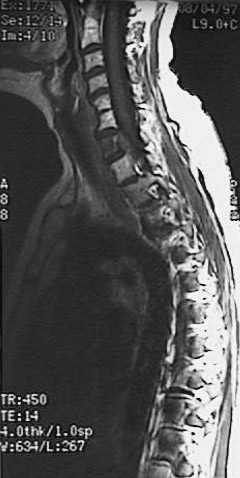

This magnetic resonance imaging (MRI) scan of the spine in sagittal view demonstrates a

metastatic lesion destroying C7

(the first cervical vertebra is not visible in this view, and there is

partial congenital fusion of C5-C6

).